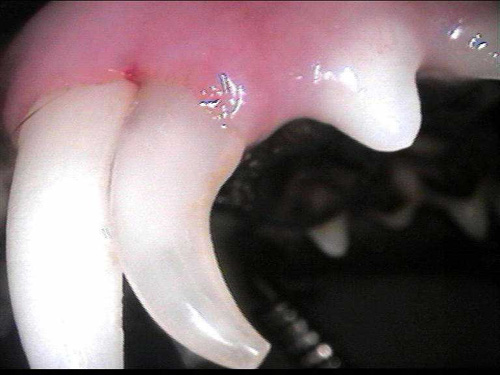

cat perio 2,5

CL1-3